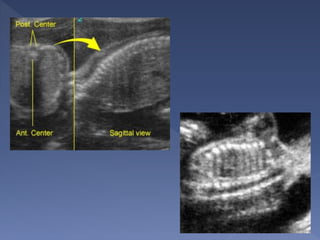

 Measure from top of head

to rump

 Always measure in neutral

position

 made between 7 to 13

weeks

 Very accurate(Dating

with the CRL can be

within 3-4 days of LMP)

 it should not be changed

by a subsequent scan.